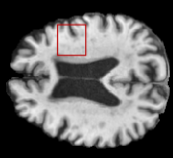

Table 2: Segmentation results for all proposed methods, each column represent a different slide in the image, blue areas are regions which were correctly labeled, false positives are shown in green, and false negatives in yellow

In order to better understand the above results, we visually analyzed the output segmentation performed for each method. Table 2 shows the results for three different slices (one slice per column). As illustrated, the proposed method is able to produce less false positives. It is also important to note that, unimodal segmentation is the one that produces more false positives, showing the advantage of using synthetic data. Regarding the nature of false positives, it can be easy to see in the third column a large number of false positives are on the border of periventricular lesions for the Unimodal method in comparison to the proposed method. Also from the first and second column, it can be observed that Unimodal tend to produce more small regions of false positives near to cortical areas. Removing such false positives requires additional post-processing steps, therefore, it is of value avoid this kind of over-segmentation. It can also be noted that synthesis methods tend to produce the same kind of false negatives, this may be due to the blurring effects in synthesized images since the information available during testing is limited – which otherwise is available from a FLAIR sequence.